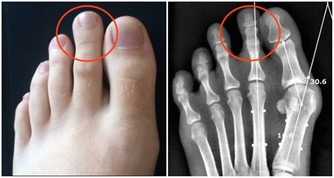

因此,“春捂”應重點做好手腕、腰部、肚臍、小腿及雙腳保暖。

厚褲和厚襪不可過早減去,並常用熱水泡腳,睡覺時下半身蓋厚一點。

下身的褲子、襪子、鞋子,一定要穿得厚點,暖和點,而上身略減則無大妨礙。